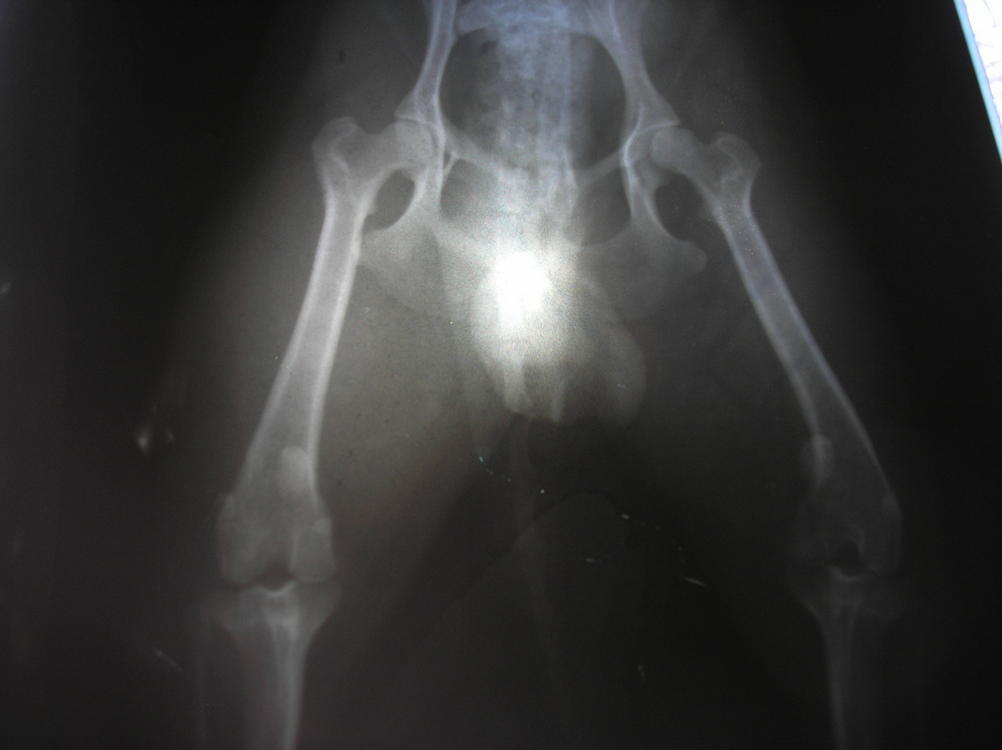

Мы сегодня сделали рентген с анестезией, на правом 2ая степень, на левом нестабильность, т.е. 1ая степень...травматолог говорит нужна операция, день правда еще не назначили...:flushed:

Вот наши результаты:

Я не отказалась, т.к. по этому рентгену даже я увидела все это!(

Плюс его нормально осмотрели (пока под наркозом был), правая коленка совсем болтается и левая тоже нестабильная. Завтра закажут все материалы специально для Тоськи и назначат день. На левой травматолог хочет укрепить связку, чтобы вывиха не было, а правую оперировать по полной! Надеюсь, нам это поможет жить полноценной жизнью, а пока покой-покой-покой!